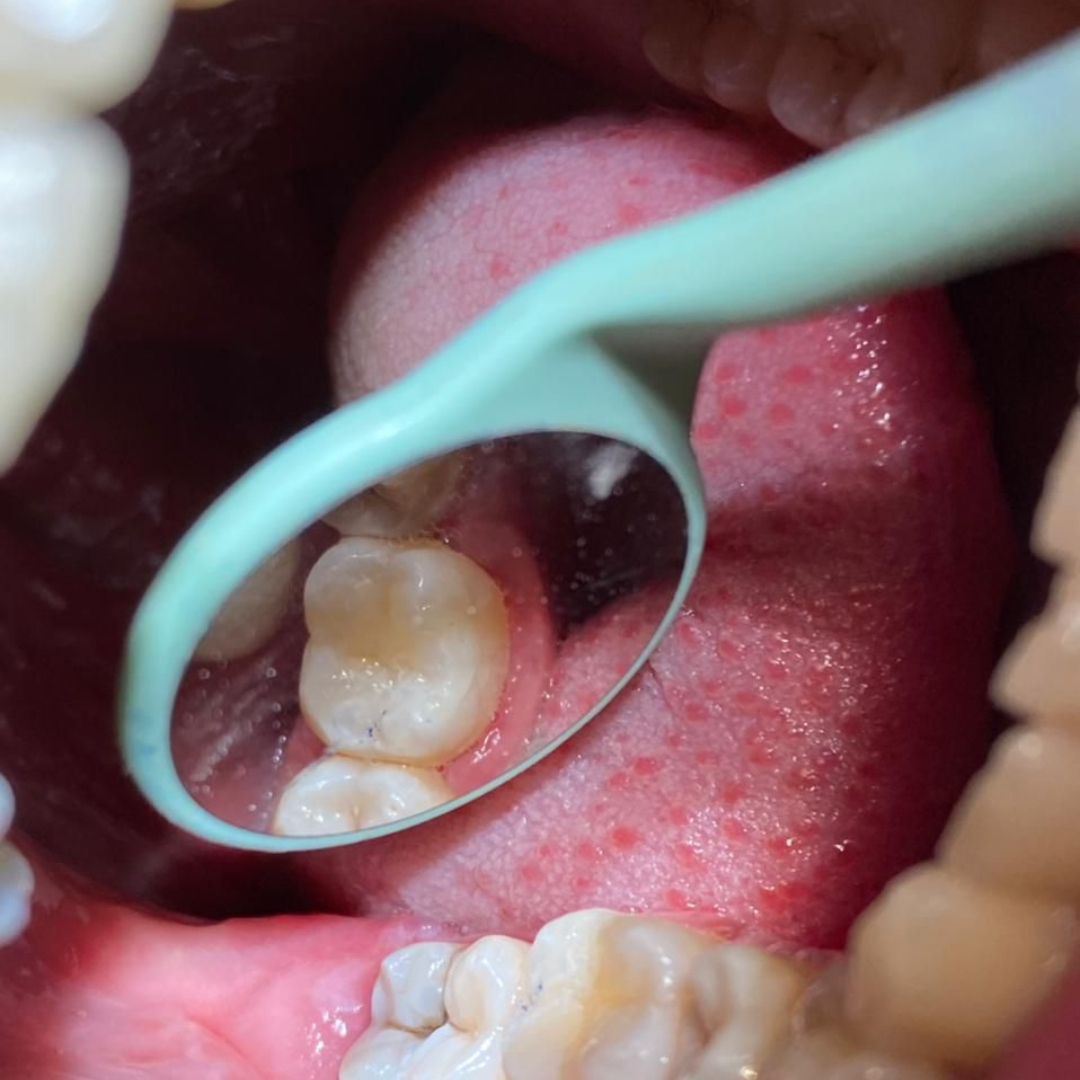

Throughout my studies, I immersed myself in learning, not just from books, but through hands-on experience at a local dental clinic. I spent countless hours there, treating patients and gaining invaluable practical skills. The joy and relief I saw in their eyes after each session were my greatest rewards. My humility and dedication earned me the love and respect of everyone around me.